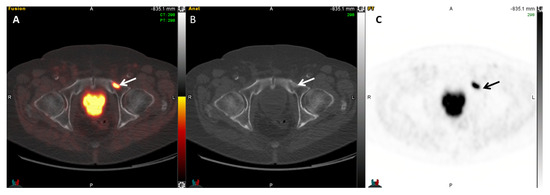

2.4. 18F-Fluciclovine (FACBC) PET

- Nanni, C.; Zanoni, L.; Pultrone, C.; Schiavina, R.; Brunocilla, E.; Lodi, F.; Malizia, C.; Ferrari, M.; Rigatti, P.; Fonti, C.; et al. 18F-FACBC (anti1-amino-3-18F-fluorocyclobutane-1-carboxylic acid) versus 11C-choline PET/CT in prostate cancer relapse: Results of a prospective trial. Eur. J. Nucl. Med. Mol. Imaging 2016, 43, 1601–1610. [Google Scholar] [CrossRef]

- Schuster, D.M.; Nieh, P.T.; Jani, A.B.; Amzat, R.; Bowman, F.D.; Halkar, R.K.; Master, V.A.; Nye, J.A.; Odewole, O.A.; Osunkoya, A.O.; et al. Anti-3-[18F]FACBC positron emission tomography-computerized tomography and 111In-capromab pendetide single photon emission computerized tomography-computerized tomography for recurrent prostate carcinoma: Results of a prospective clinical trial. J. Urol. 2014, 191, 1446–1453. [Google Scholar] [CrossRef]

- Gusman, M.; Aminsharifi, J.A.; Peacock, J.G.; Anderson, S.B.; Clemenshaw, M.N.; Banks, K.P. Review of 18F-Fluciclovine PET for Detection of Recurrent Prostate Cancer. Radiographics 2019, 39, 822–841. [Google Scholar] [CrossRef]